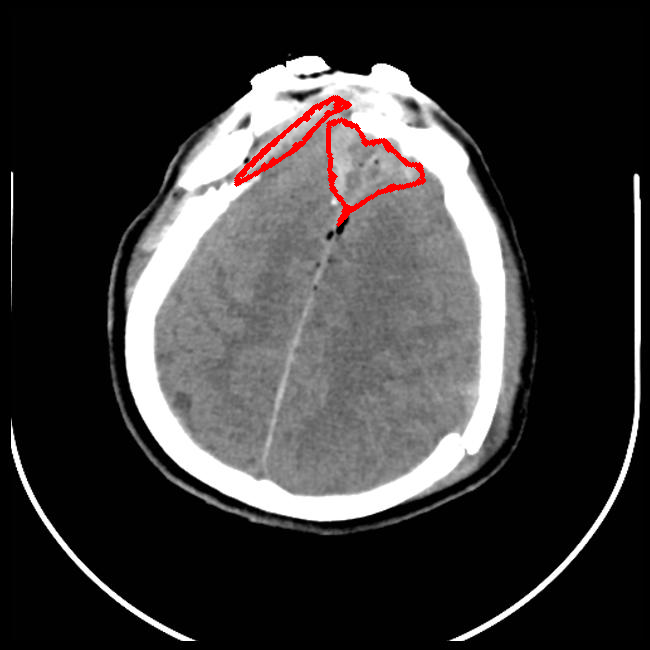

Limited Angle

CT GMAIMMbench Disease Diagnosis

Limited Angle - L0 (Original)

L0

L0 (Original)

Limited Angle - L1 (Moderate)

L1

L1 (Moderate)

Limited Angle - L2 (Severe)

L2

L2 (Severe)

Question

This is a CT image. Which of the following options is the most appropriate to demonstrate the marked area?

A brain hemorrhage B barrett's esophagus C thyroid nodule D retinal hard exudates

Ground Truth: A. brain hemorrhage